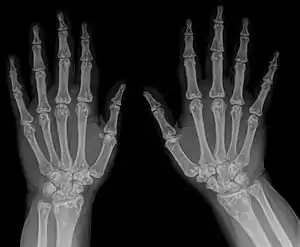

It is a genetic disorder associated with LEMD3.[6][7] It is inherited in an autosomal dominant manner.[2] In a very few, X-rays may show several areas of compact bone.[1] Conditions that may appear similar include tuberous sclerosis, pseudoxanthoma elasticum, neurofibroma, and lipoma, among others.[1]

- X-ray

Osteopoikilosis